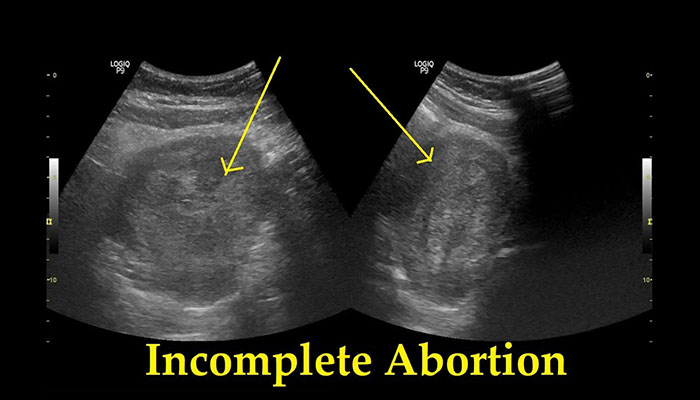

ইনকম্প্লিট এবর্শন | Incomplete Abortion